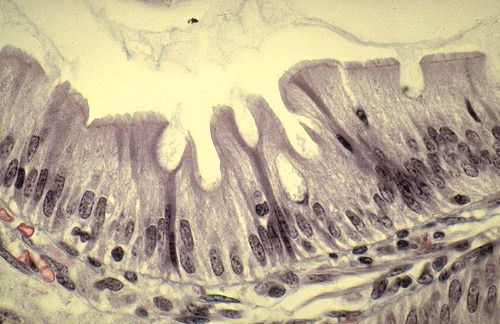

BORDURE EN BROSSE-

Prismatiques : intestin